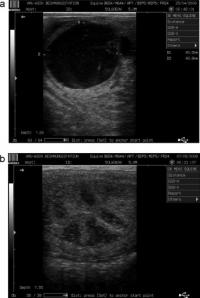

• 3.3. Follicular development, follicular hormone production and ovulation